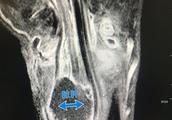

Silver-colored silver accepted operation treatment, left lower limbs by amputation. Suffer the person that visit to offer a plan

Now afternoon, new capital signs up for a reporter to understand from Yunnan orthopaedics hospital, silver-colored silver on March 19 before dawn is sent this courtyard cure, because the condition of an injury is more serious, left to its lower limbs became amputation operation. Silver-colored silver already turned to common ward from ICU afternoon at 20 days, the illness is relatively stable, consciousness is already sober.